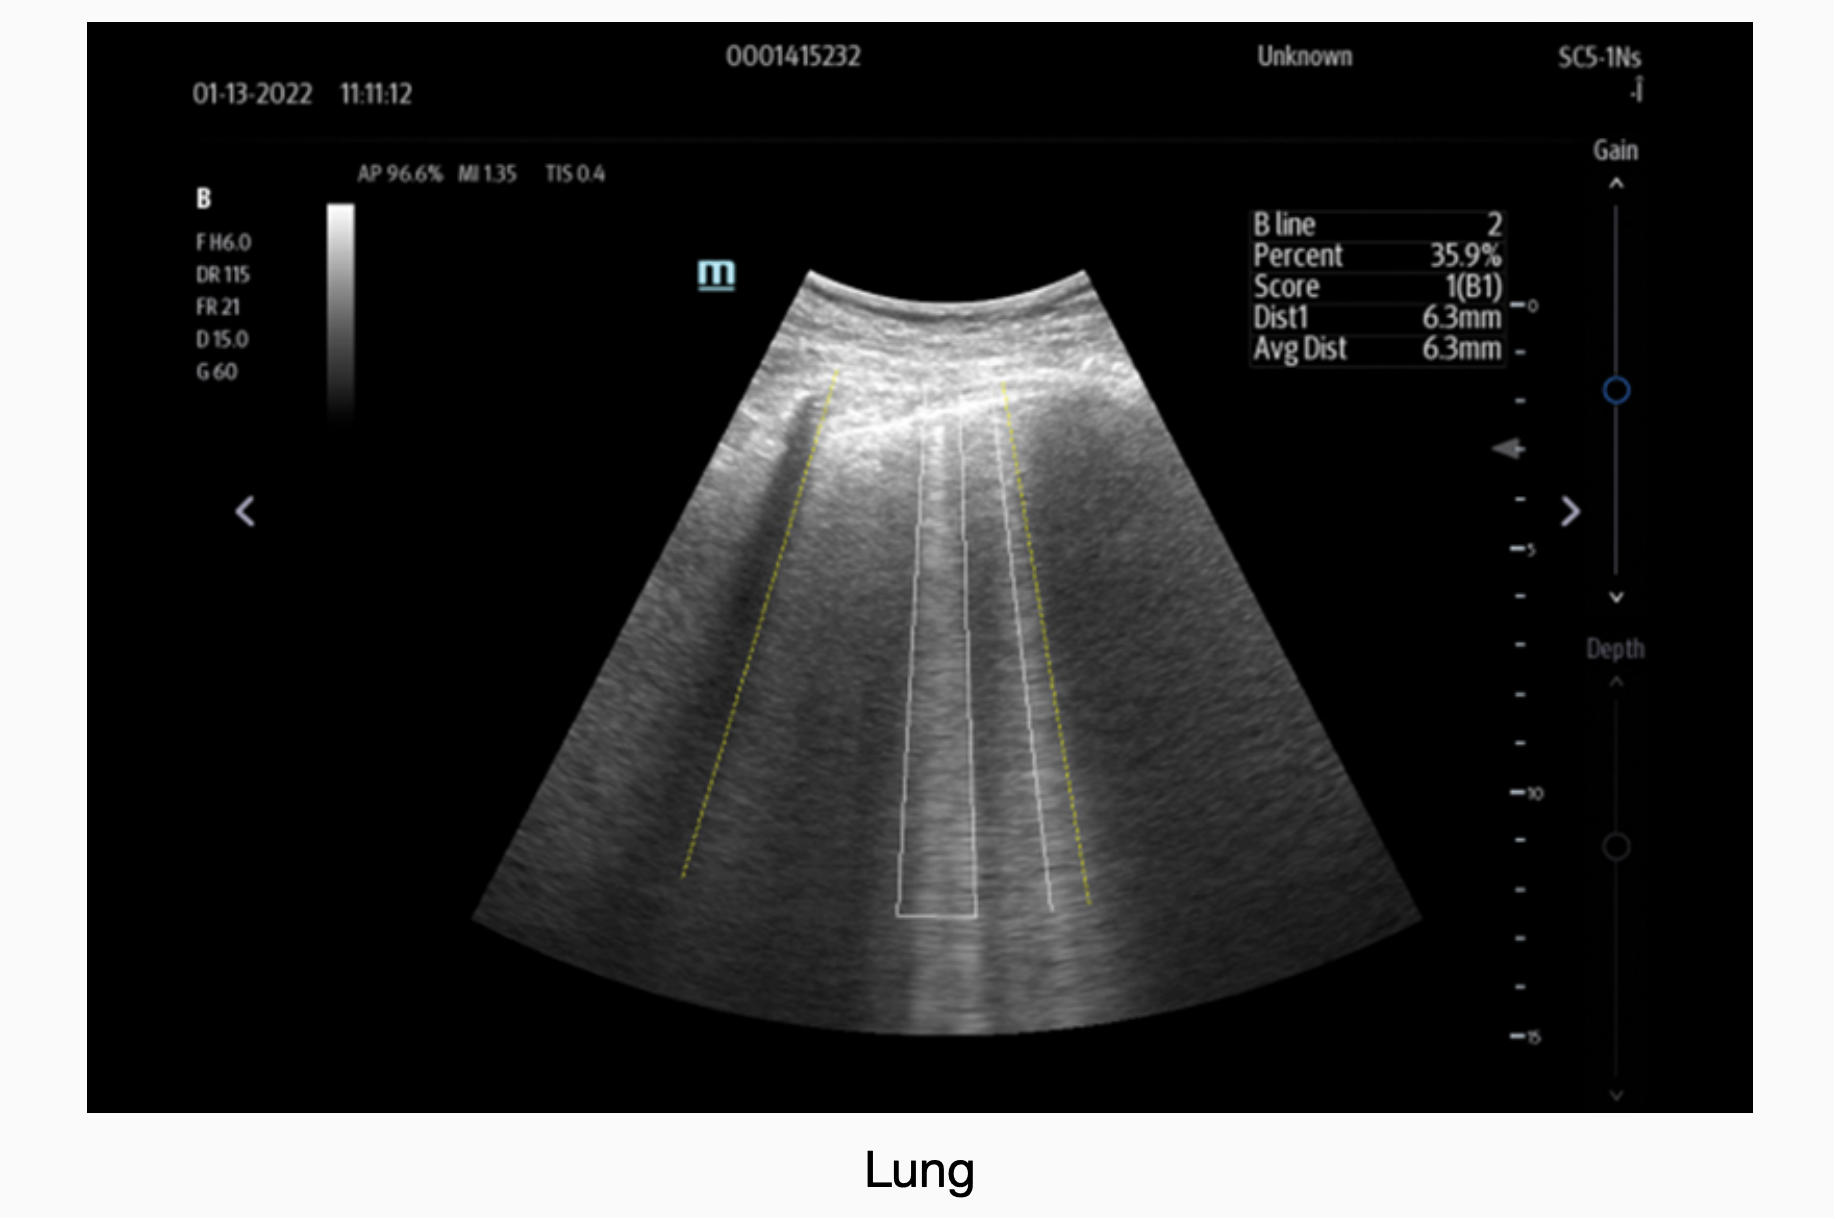

Clinical Images